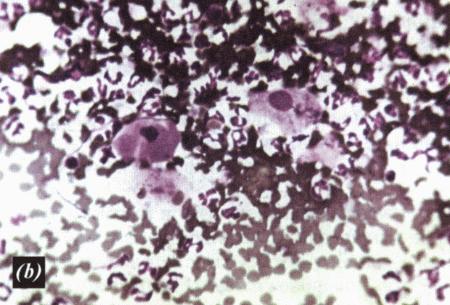

Фиг. 3.8.

Большие скопления нормальных эпителиальных клеток эндометрия в эндометриальном цитологическом образце, взятом у суки грейхаунда в начале метэструса (образец окрашен Diff-Quik®) (Воспроизведено с разрешения из Journal of Small Animal Practice (1998) 39, 2–9).